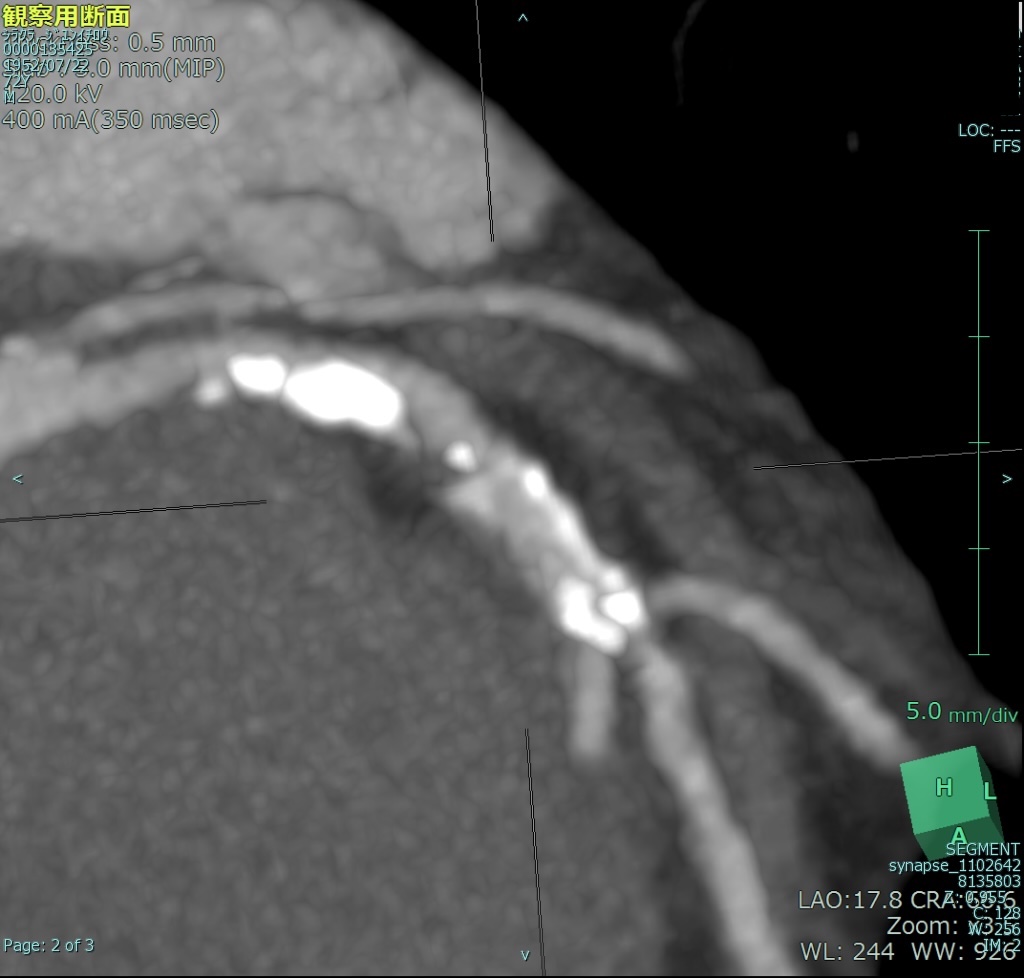

The cardiac CT demonstrated stenotic lesions in the left anterior descending artery and circumflex artery (Fig 1).